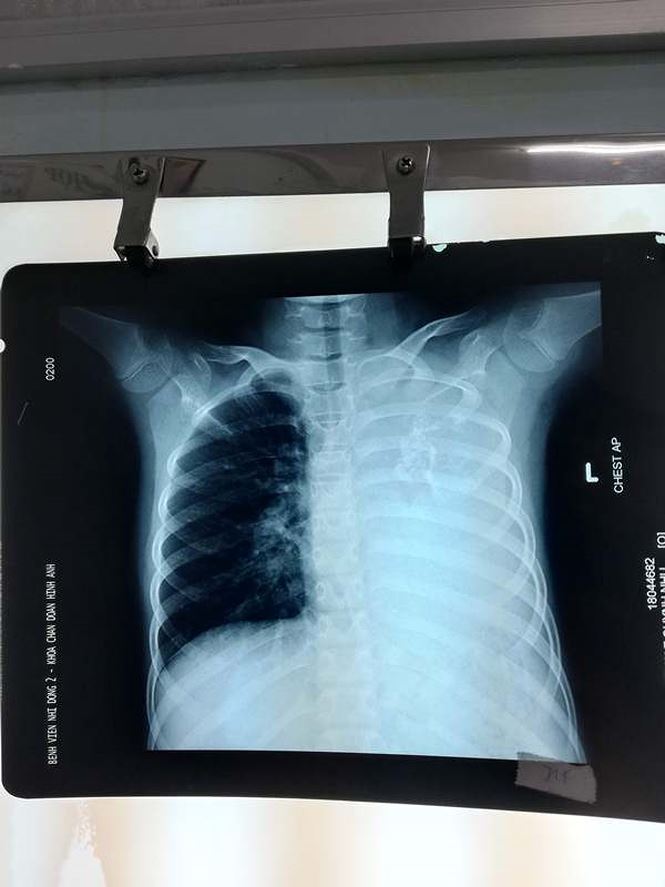

Theo các BS, bệnh nhi được người nhà đưa đến BV Nhi Đồng 2 khám do tình trạng ho kéo dài, khó thở khi gắng sức. Qua hình ảnh CT scan ngực, các BS đã phát hiện một khối u phổi khổng lồ xâm lấn toàn bộ phổi trái gây tắc đồng thời phế quản gốc trái và động mạch phổi trái khiến bệnh nhi chỉ hô hấp bằng 1 phổi bên phải.

Hình ảnh khối u trên phim X-Quang. |

Đánh giá đây là một ca mổ vô cùng khó khăn và nguy hiểm, ê kíp mổ đã quyết định chỉ sinh thiết u bằng kim với hy vọng nếu là khối u ác tính thì hóa trị sẽ giúp thu nhỏ kích thước nhờ đó cuộc mổ khả thi và an toàn hơn. Tuy nhiên, kết quả sinh thiết cho thấy đây là khối u nguyên bào sợi cơ quanh phế quản bẩm sinh (tiếng Anh là congenital peribronchial myofibroblastic tumor).

ThS.BS Vũ Trường Nhân, phó khoa Ngoại tổng hợp BV Nhi Đồng 2 cho biết, đây là một khối u cực hiếm và thuộc loại giáp biên ác tính không đáp ứng với hóa trị. Theo tài liệu của WHO tính đến nay, chỉ có 16 trường hợp được báo cáo trên thế giới và thường được phát hiện ở lứa tuổi sơ sinh nhờ vào chẩn đoán tiền sản.